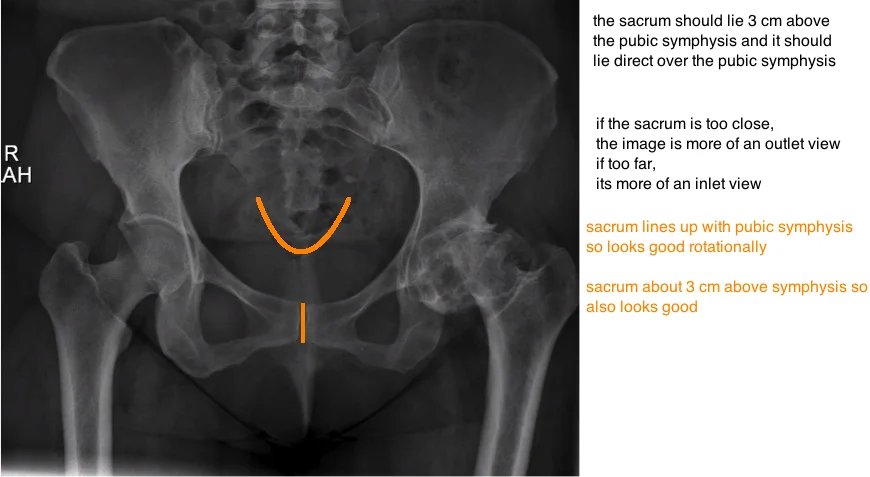

evaluating pelvic tilt on ap xray